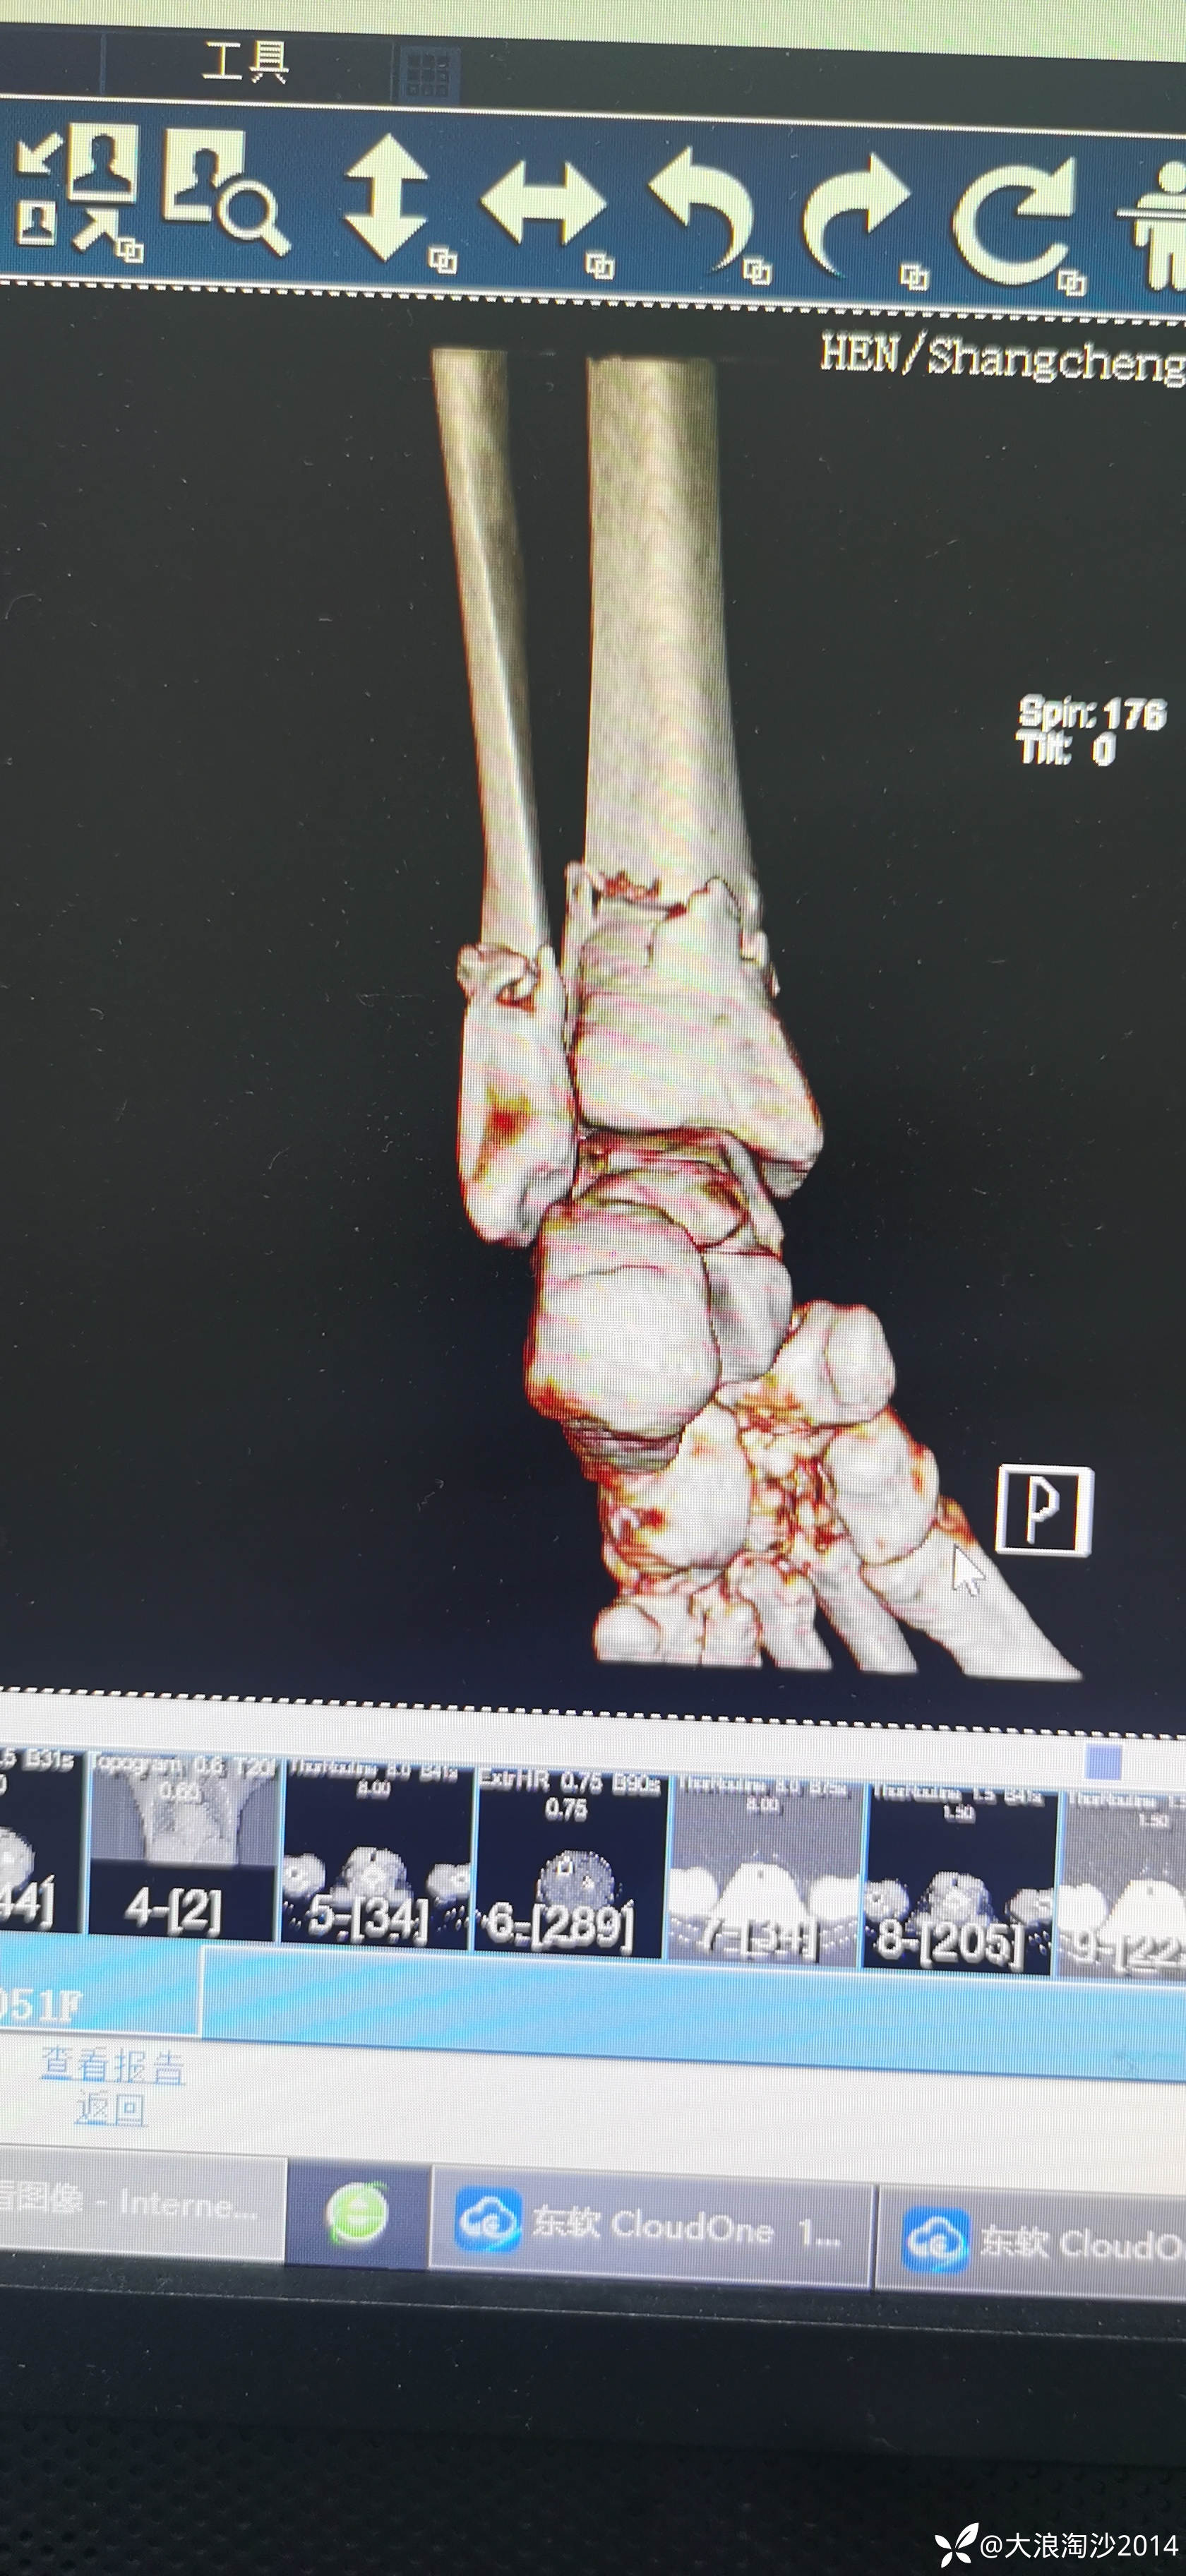

一65岁女性患者,偏瘦,体重75斤,车祸外伤致左胫腓骨远端骨折,入院后消肿后,病人可以用皮包骨头形容,考虑胫骨远折端不适合用内侧插板(mippo技术),病人太瘦,如取两个切口分别处理胫腓骨,切口容易出现问题,因此采用前外侧一个切口处理胫腓骨远端骨折(片子顺序上传有点乱)